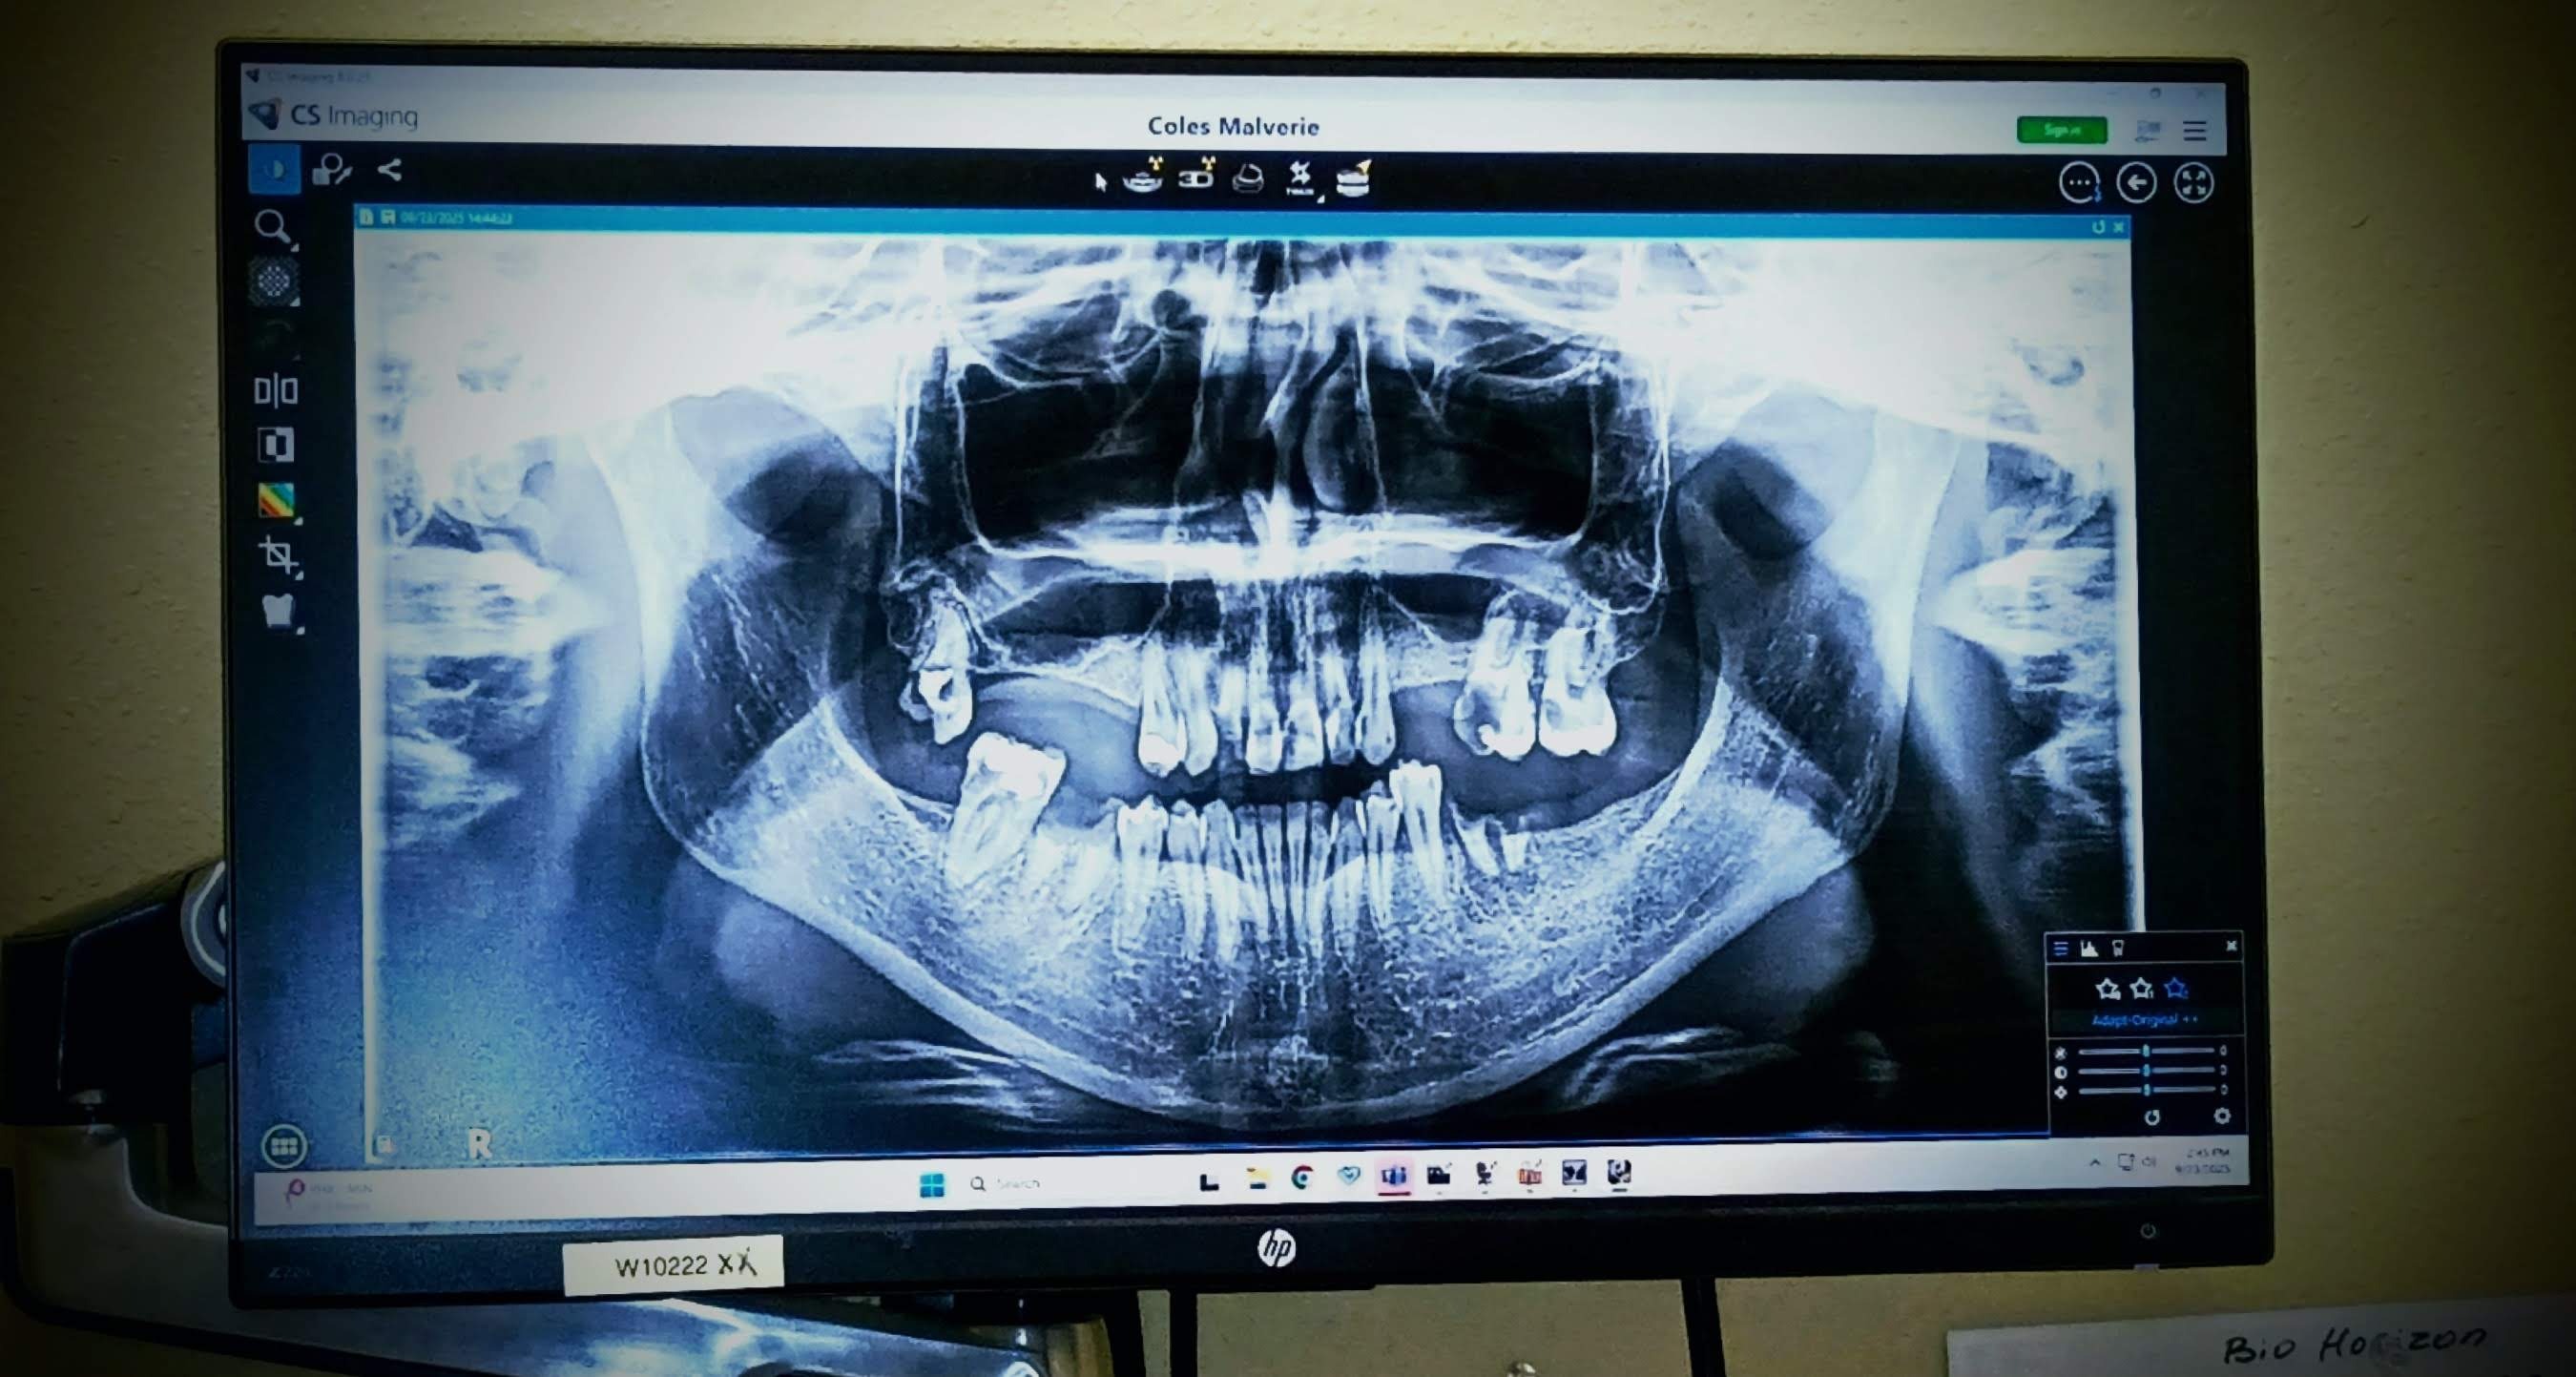

My name is Malverie, and I am reaching out to my community for support as I face a significant medical challenge. I am in need of permanent dentures or dental implants, which are essential not only for my personal confidence and oral comfort but also for protecting my oral health and potentially my overall well-being. This journey has been difficult, and the costs associated with these procedures are more than I can manage on my own.